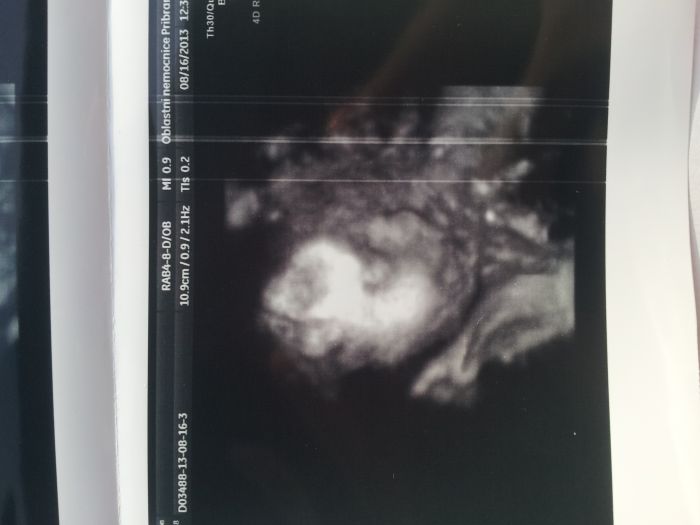

Jo a takhle se nám malá předvedla. Pořád byla zamračená, ale pak se na nás usmála

A na té druhé fotečte asi poznáte co to je. To je (tu už několikrát zmiňované) ..kávové zrníčko.. Holka jako lusk panečku

Vloženo z mobilu, tak se omlouvám, že je to obráceně